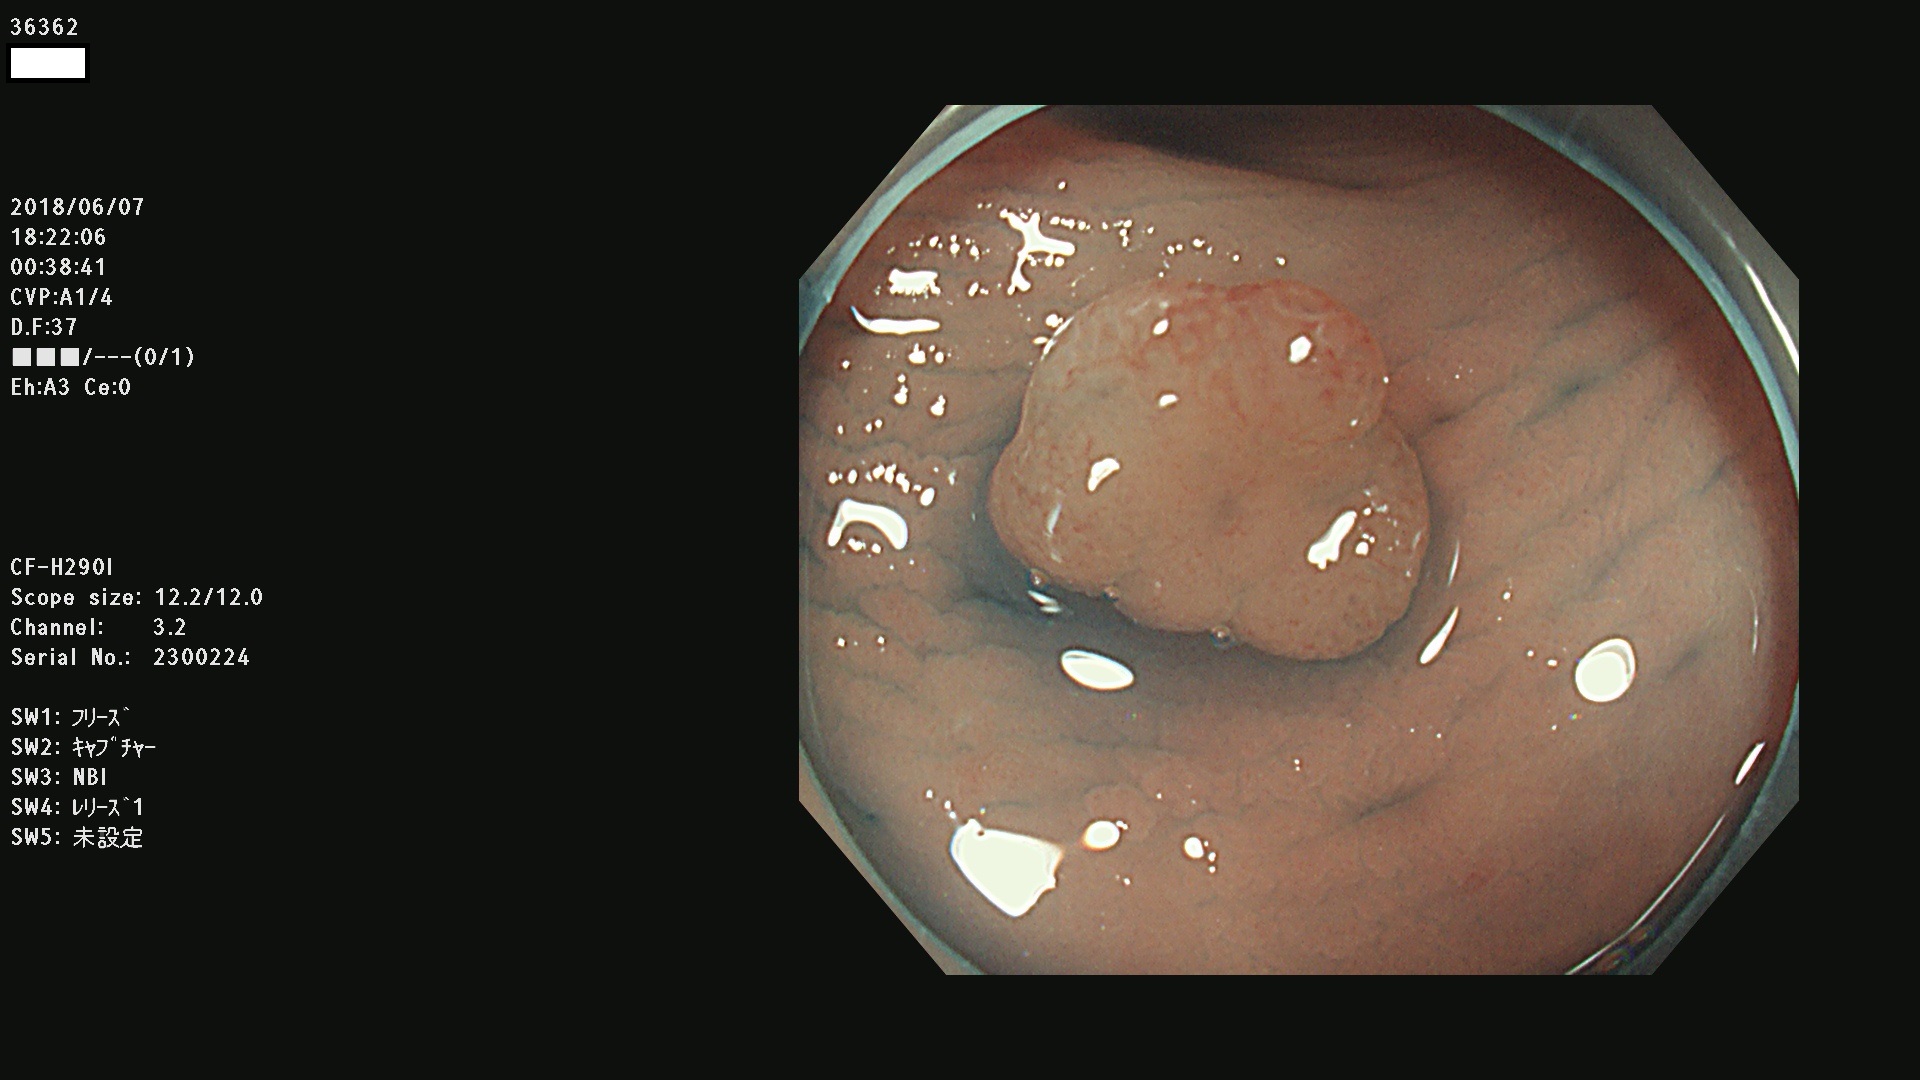

発見困難で危険性の高い平坦型病変(上記100名より抽出) ![]()